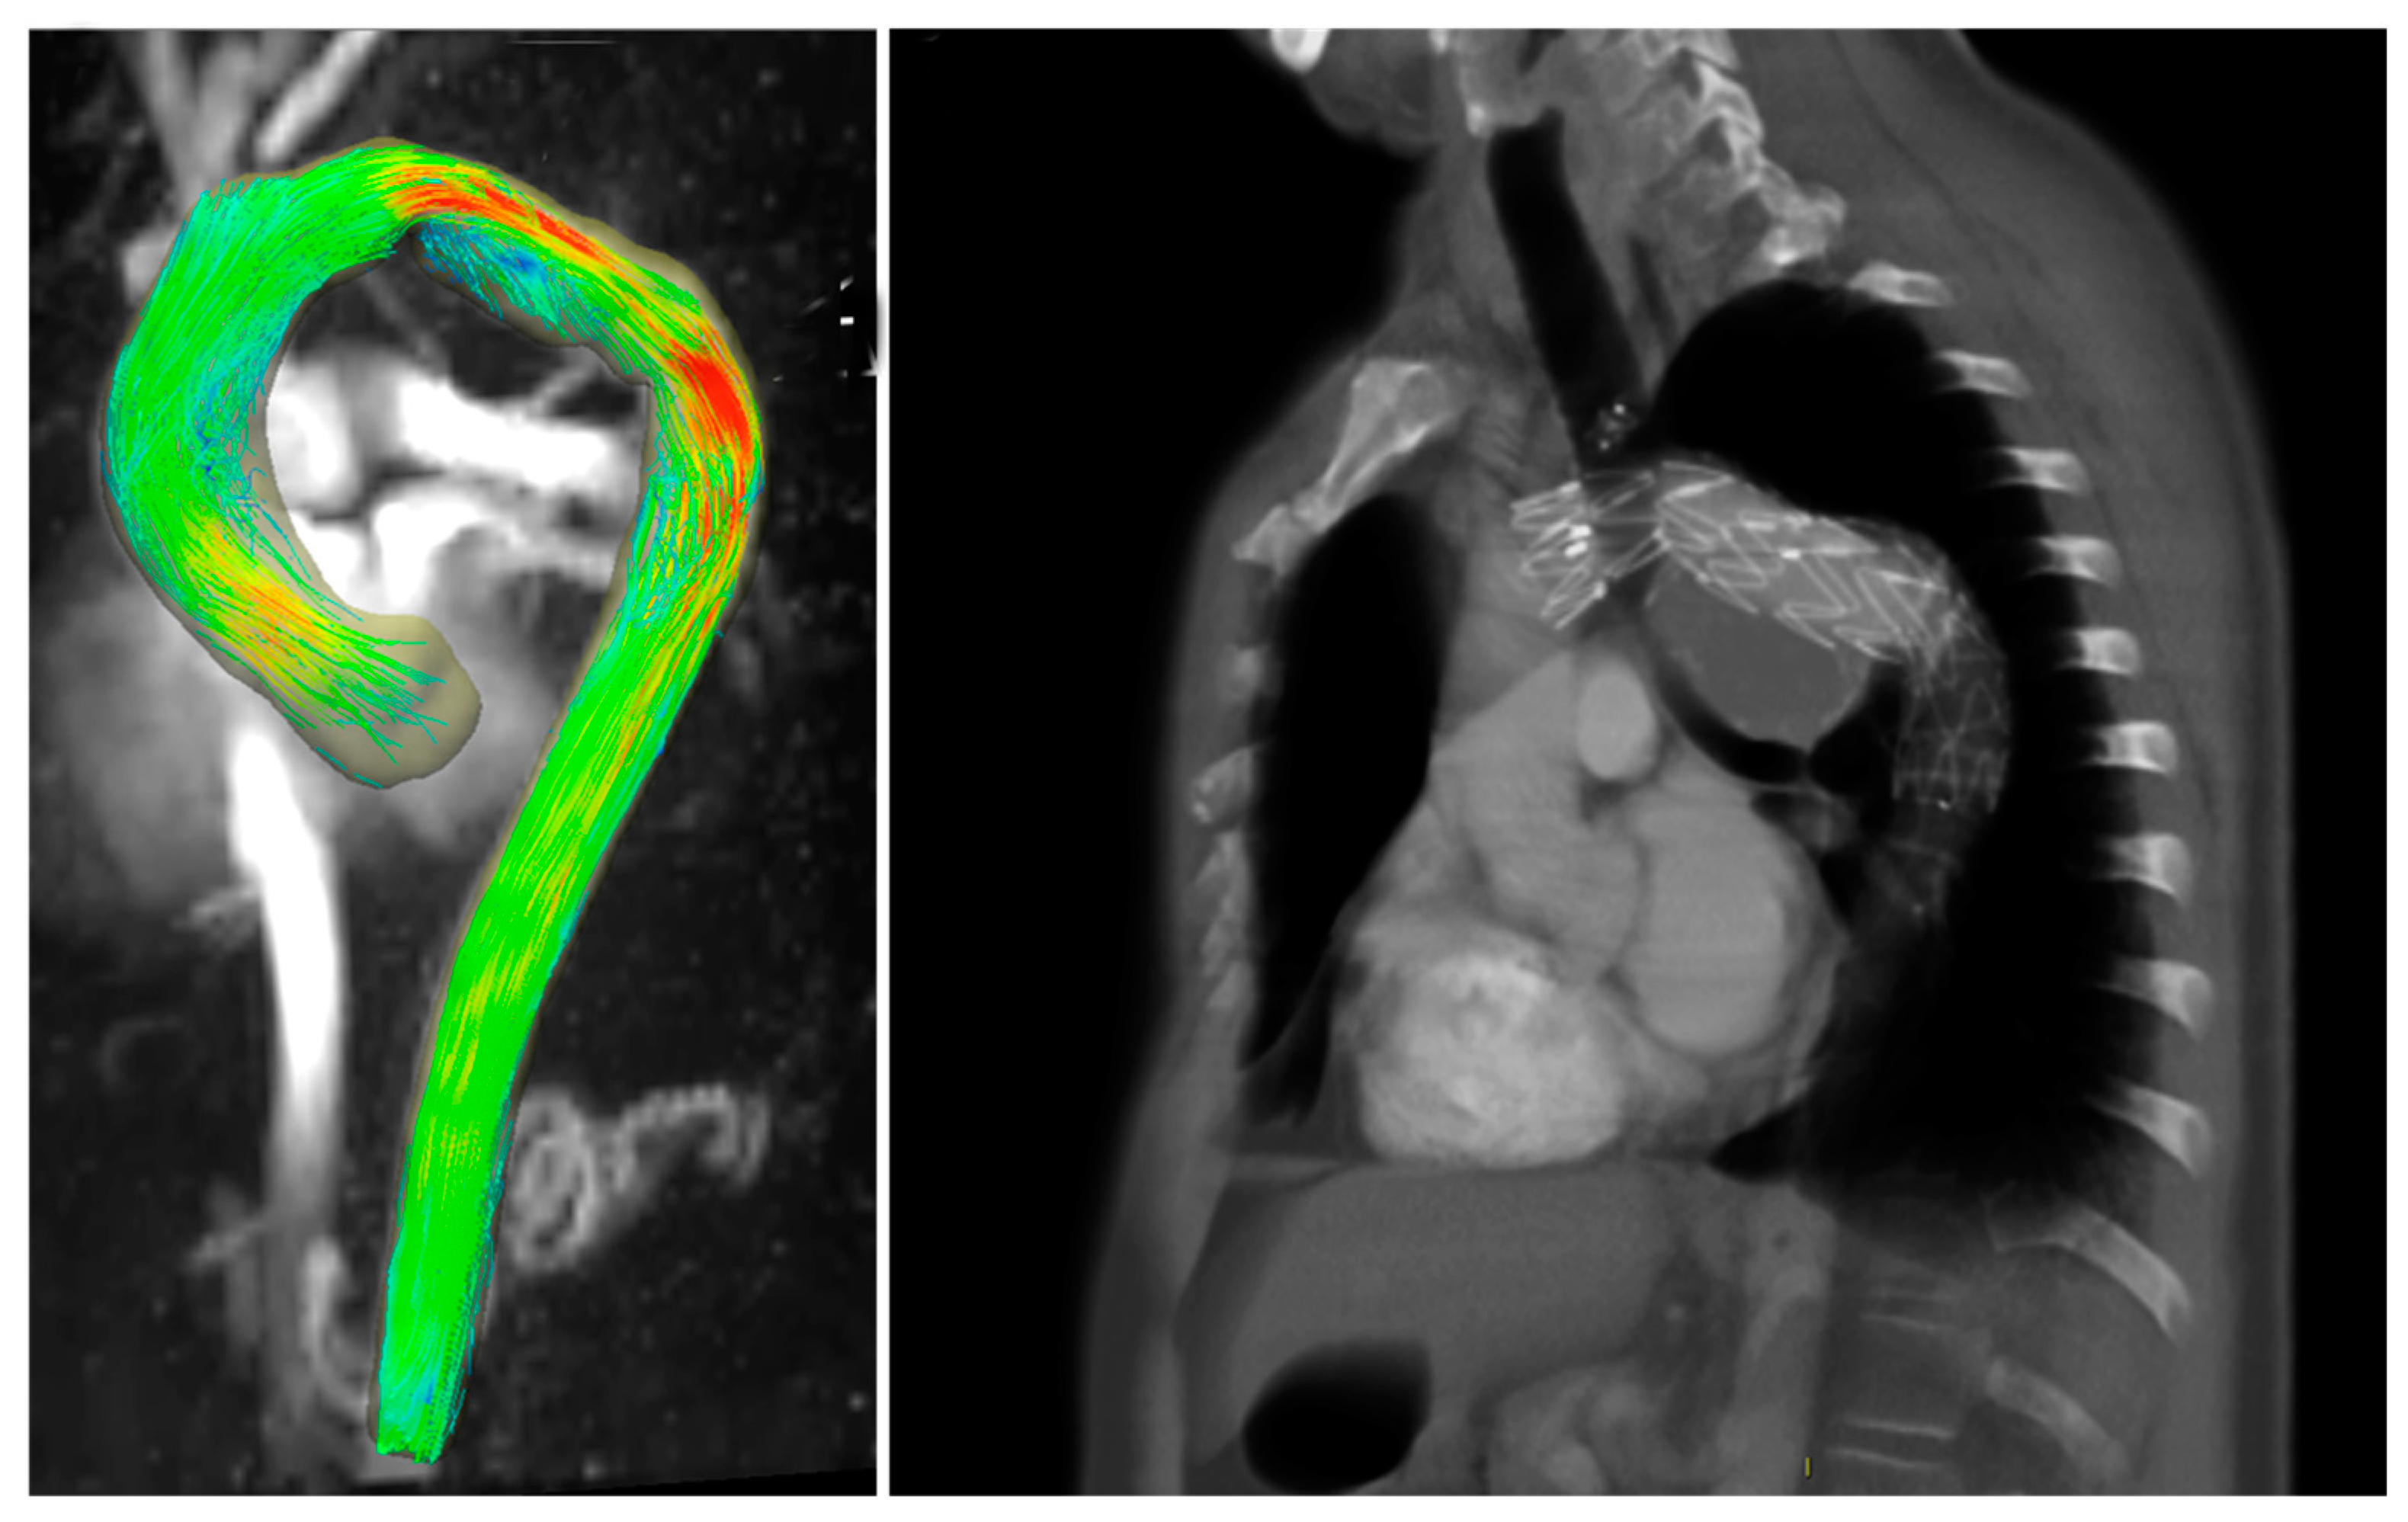

Four-Dimensional Flow MRI for the Evaluation of Aortic Endovascular Graft: A Pilot Study

3. Results